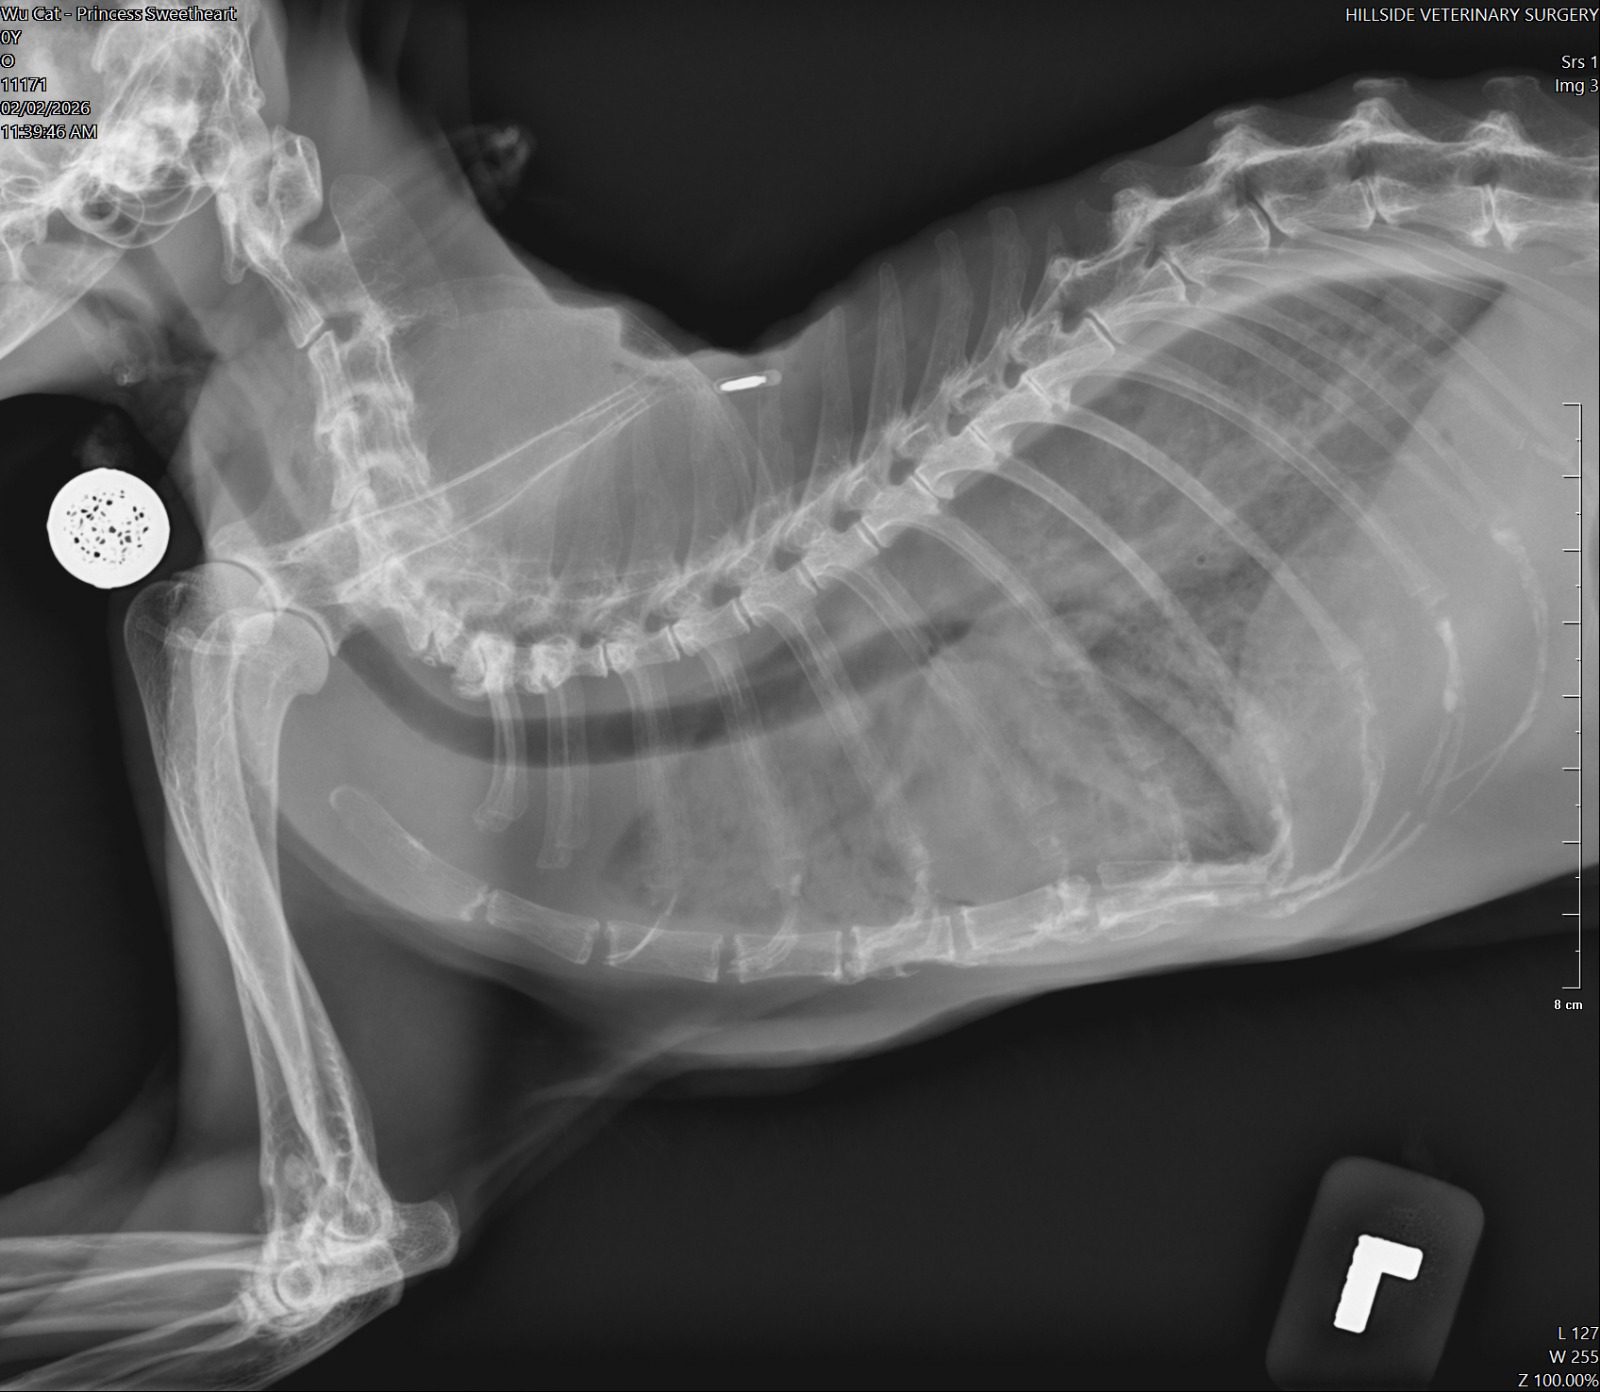

10am+: enter to bring boy for review, princess sianz look. Sleeping even though jo is serving food alr. Weird. I Subcut her as routine but i find her breathing labour. She is really weird. I feel that she might collapse. Jo serve tuna w gravy she is not keen, lucky when I serve tiny pouch she is keen but only take in 5%? Something very wrong she is 喘。 rush her to hillside w ah boy. Alison ard, she bring Ps in first to check, told her Ps is the heart/kidney combo. I taken her RR b4 she go in: 56.

11.15am: Dr Cheryl update: her o2 level low 80% only, she is going to take chest X-ray. most prob is fluid overload her heart le. She wanna retake her bloods, and most prob start frusemide which will stress the kidney but better than if the fluid can’t clear by kidney on time, her heart will fail and she die. That’s what I’m worrying about that why I bring her in cos I know heart scarier. She needs to stay in clinic in o2 for hours, cos to jab frusemide need to monitor in o2. Target 4.00-6.00pm.

Can hear from dr Cheryl tone: it’s serious. Later see the X-ray see how bad. I’ll definitely got to talk to princess let her relax in o2 n wait for me to fetch her when she feel better.

12.50pm; blood drawn, kidney aren’t as bad. Is her heart cannot take it. Lung full of fluid, can’t see her lung so she is a little drowning now, just hide very well. Frusemide given at 12.15pm, only can let frusemide do the job of draining fluid from lung. Can’t poke to draw cos not fluid ard lungs. Dr. Cheryl says Sure (high possibility) die by today. She is not flat yet, definitely panting, knew I’m here again. Sayang her n her head will tilt to me, move a little panting. I didn’t open her cage anything more than 20s. Let her max the use of o2.